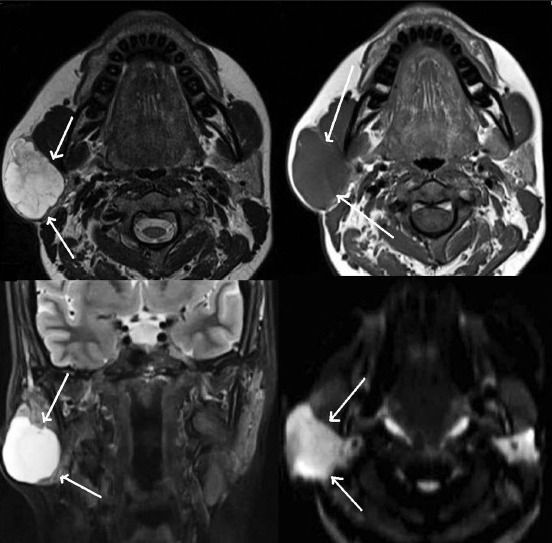

Последовательность STIR во фронтальной плоскости (а) и Т2-взвешенное изображение в горизонтальной плоскости (с): увеличение правой околоушной железы с неоднородной низкой интенсивностью сигнала. Т1-взвешенное изображение во фронтальной плоскости (b): умеренное усиление железы после введения гадолиния в связи с хроническим сиаладенитом.

Информативна ли МРТ слюнных желез при сиаладените

- Нечеткие края

- Высокая интенсивность сигнала на Т2-взвешенном изображении

- Низкая интенсивность сигнала на Т1-взвешенном изображении

- Выраженное усиление после введения гадолиния

- Размытые границы и распространение на окружающую жировую ткань и жевательные мышцы с повышенной интенсивностью сигнала на Т2-взвешенном изображении.

- Неоднородный сигнал с низкой интенсивностью на Т1 -взвешенном изображении и высокой или промежуточной интенсивностью на Т2-взвешенном изображении

- В случае длительного течения сиаладенита часто наблюдается атрофия железы со снижением интенсивности сигнала.